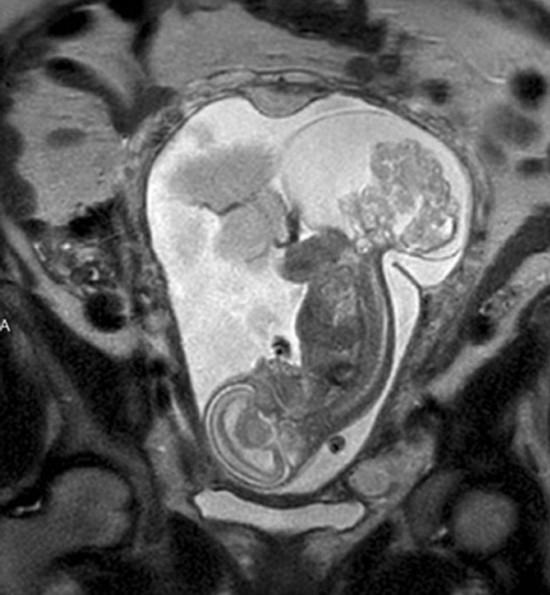

胎儿16周被取出子宫手术 36周后健康出生(2)